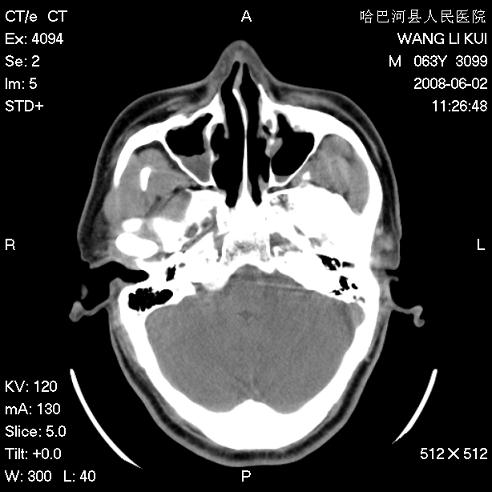

标题: CT13803:反复性鼻塞、流涕一年余 [打印本页]

标题: CT13803:反复性鼻塞、流涕一年余

副鼻窦炎,右上额窦积脓。左眼肌锥内见致密影,视神經受压

1.全组副鼻窦炎2.双侧上颌窦积液

1)全副鼻窦炎(左侧上颌窦黏膜下囊肿或息肉)。2)左眼眶肌锥内不规则小结节状软组织密度影;考虑为小血管瘤可能。建议行ct增强扫描检查。

全组副鼻窦炎,左侧肌锥内不规则形软组织肿块影,与眼外肌密度相当,左侧视神经受压,肿块与视神经及眼外肌分界清晰,眼外肌无增粗,眶壁无破坏,球后脂肪间隙不模糊,考虑良性改变,小血管瘤或神经源性肿瘤可能,建议增强扫描。

谢谢,增强扫描做了,眶内病灶与海绵窦同步明显强化,血管瘤